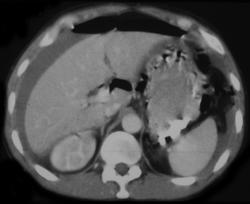

Subtle Gastric Cancer Nearly Missed By Food in the Stomach